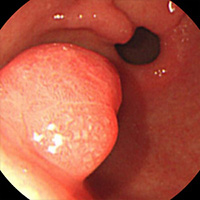

식도 및 위용종

• 주변의 점막보다 안쪽으로 돌출한 모든 병변을 용종이라고 하며 식도에 발생한 것을 식도용종, 위에 발생한 것을 위용종이라고 합니다. 하지만 좁은 의미로는 선구조를 가진 상피세포에서 기인한 것만을 말합니다.